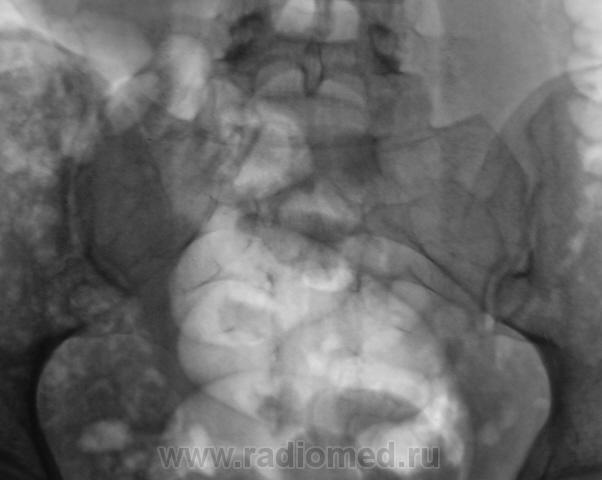

Из анамнеза известно, что примерно 2 месяца тому "летела" со сноутборга около 200 метров. Сейчас беспокоят боли в области спины, крестца и лонного сочленения. УЗИ было сделано всего, что только можно, везде - "норма". Хирурги, вроде-бы тоже ничего не находят. Но боли, видать значительные, походка вынужденная. На рентгенографию была направлена, как жест отчаяния, мол может быть, что-то найдут.

Так как "содержимое кишечника" не способствовало анализу изображений, пациентке было предложено, посетить кабинет повторно.

Рентгенограмма в прямой проекции.

Посттравматический симфизит - это такой медицинский диагноз есть? Тогда уж лучше - симфизопатияУлыбаюсь.  По поперечному перелому Л5 - тангенциальный эффект, сложение теней. По хорошему, надо бы доснять поясничный отдел позвоночника, в том числе в косых проекциях - на дугоотростчатые суставы, и грудо-поясничный переход.

- единственное что ещё увидел - п/травматический остеохондроз/остеоартроз Cs 2-Cs 3 (а, может, и до травмы так было?.. -

1. По первым снимкам не отпускало впечатление о повреждении левого крестцово-подвздошного сочленения. После подготовки вроде-бы все нормально, но все равно что-то гложет.